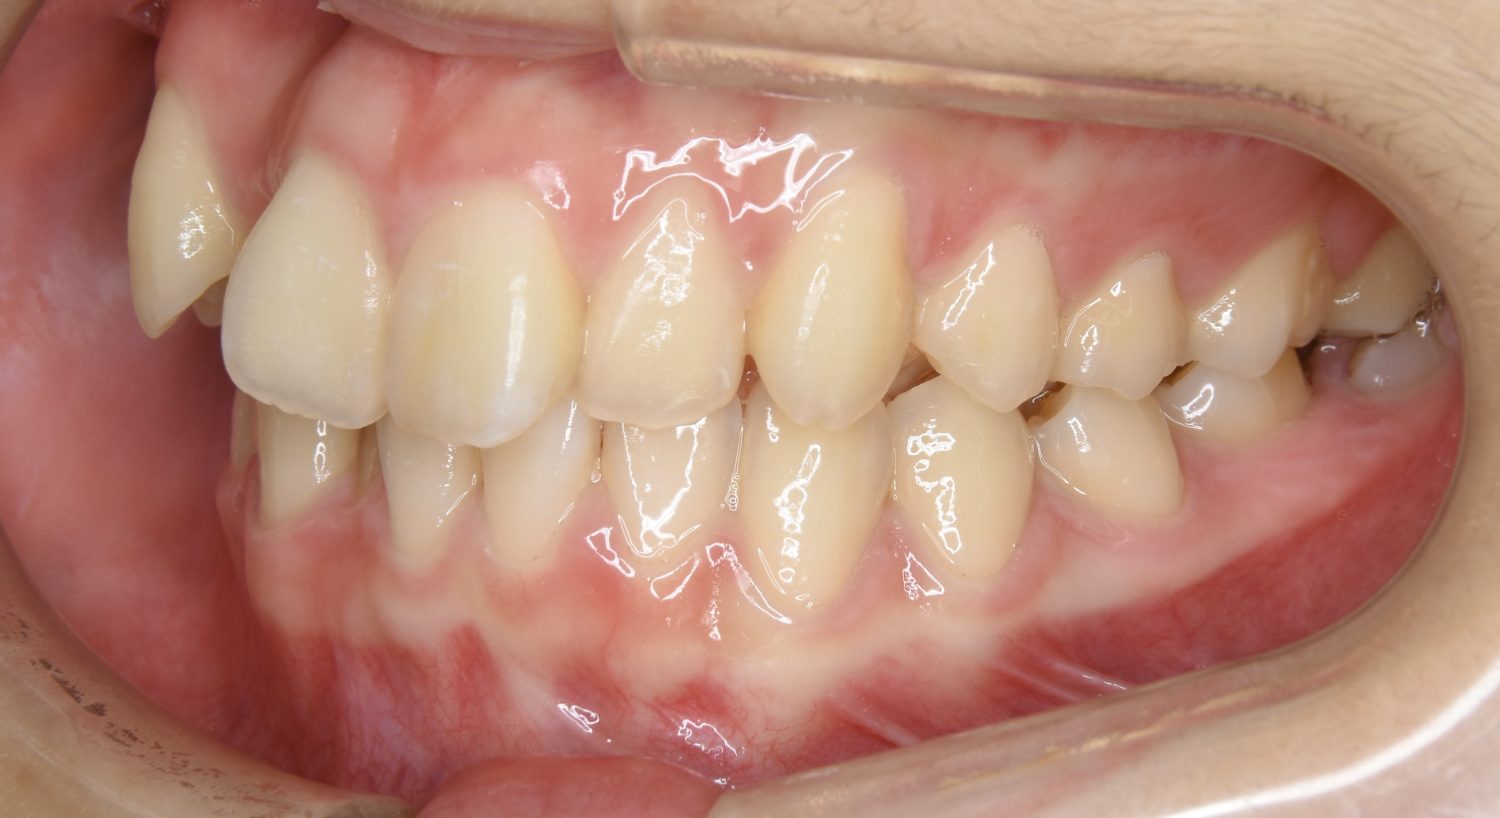

叢生の症例紹介②

Before

After

主訴

歯の凸凹を治したい。

治療内容

アライナー(インビザライン)にて非抜歯で治療を行いました。

上下前歯部に叢生(凸凹)が認められる状態でした。歯列の遠心移動を行うことで機能面および審美面が改善されました。